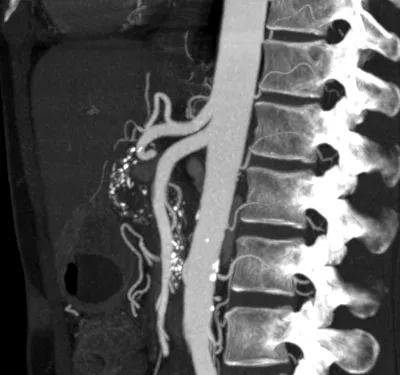

This collection contains 1 radiology images related to angiogram, including various imaging modalities such as X-rays, MRIs, CT scans, and ultrasound images commonly used in medical diagnosis and education.